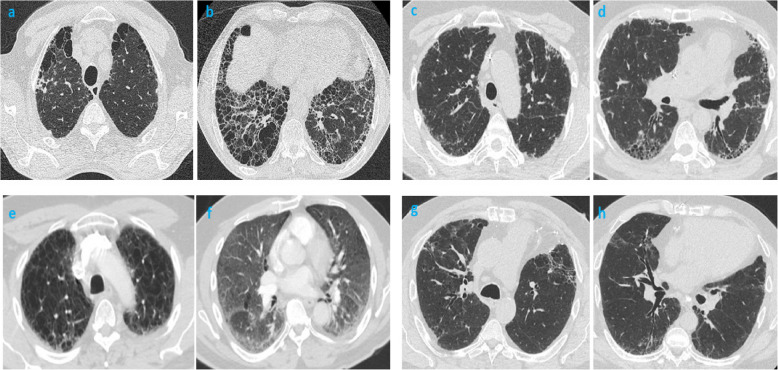

Results: The study cohort (n=556) was divided into groups: coal-/smoking- (8.3%), coal-/smoking+ (26.6%), coal+/smoking- (22.3%), and coal+/smoking+ (42.8%). Miners were older males with a median duration of coal mine work (CMW) of 30-years. Ever-smokers (66% of miner cohort and 76% of non-miner cohort) smoked 35 and 28 composite pack years (CPY) respectively, where miners had greater intensity of smoking (22 vs 18 cigarettes/day) compared to non-miners. On HRCT, 1/3rd and 1/5th of miners had simple and complicated coal workers' pneumoconiosis (sCWP and cCWP), respectively. 35% of ever-smoking miners had radiologic patterns for probable usual interstitial pneumonitis, nonspecific interstitial pneumonitis, desquamative interstitial pneumonitis, and combined pulmonary fibrosis and emphysema. Radiologically, both coal-/smoking+ and coal+/smoking+ showed excessive emphysema (70-80%). Histologically, miners had more fibrosis (47% and 50% in coal+/smoking- and coal+/smoking+ vs. 11% and 28% in coal-/smoking- and coal-/smoking+). Never-smoking miners demonstrated more histological evidence of CWP than ever-smokers (60% and 27%); in addition, they had radiologic and histologic emphysema (30%), radiologic interstitial lung disease (ILD) (14.5%) and histologic evidence of fibrosis (47%). Ever-smokers demonstrated histologic emphysema more frequently (33% and 67% in coal+/smoking- and coal+/smoking+ vs. 24% and 72% in coal-/smoking- and coal-/smoking+). Logistic regression modeling showed the following associations: radiologic and histologic emphysema with CPY; histologic fibrosis, any ILD (not including RB-ILD), CPFE and anthracosis with both CPY and CMW; radiologic RB-ILD inclusive of small-opacities, cCWP with both CMW and silica; and sCWP and pulmonary artery dilation with CMW. Interestingly, CPY≥30 negatively correlated with radiologic cCWP and histologic CWP. Mortality was increased in smokers (14% and 29% in coal+/smoking- and coal+/smoking+ vs. 4% and 20% in coal-/smoking- and coal-/smoking+) with predictors being radiologic ILD, histologic CWP, and related co-morbid diseases including COPD, chronic kidney disease, and gastroesophageal reflux.

Conclusion: CS demonstrated a major impact on miners' health including changing radiologic and histologic endpoints of interstitial lung diseases and emphysema.